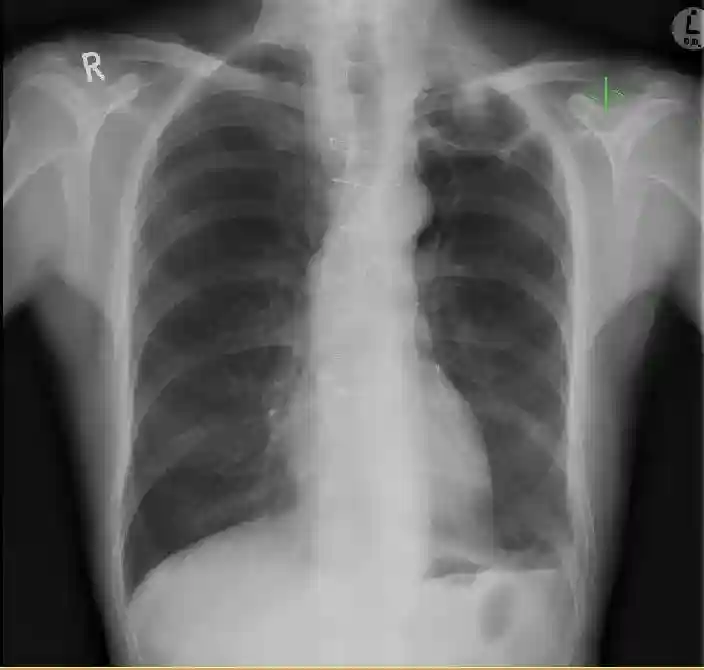

基于胸部X线片(图1)和计算机断层扫描(CT)(图2和3),做了进一步的实验室检查,并进行了支气管镜检查:

图1PA胸片显示左肺尖空洞。